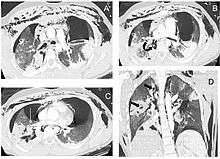

A patient with traumatic complete disruption of the right bronchus. Computed tomography scan following emergency chest tube drainage. Axial 1.25 mm thick sections with a lung window. (a) Persistent bilateral pneumothorax, pneumomediastinum and extensive subcutaneous emphysema. (b) Multiple lucencies around the right bronchial tree (curved arrow) precluding the correct recognition of the bronchial rupture. (c) The Macklin effect around the right lower pulmonary vein (white arrow). (d) Coronal view demonstrating multiple areas of alveolar consolidation in the right upper and lower lobes: intraparenchymal lucencies resulting from lung lacerations are visible on the right side (thick arrows).

Rapid diagnosis and treatment are important in the care of TBI;[6] if the injury is not diagnosed shortly after the injury, the risk of complications is higher.[18] Bronchoscopy is the most effective method to diagnose, locate, and determine the severity of TBI,[6][14] and it is usually the only method that allows a definitive diagnosis.[10] Diagnosis with a flexible bronchoscope, which allows the injury to be visualized directly, is the fastest and most reliable technique.[16] In people with TBI, bronchoscopy may reveal that the airway is torn, or that the airways are blocked by blood, or that a bronchus has collapsed, obscuring more distal (lower) bronchi from view.[3]

Chest x-ray is the initial imaging technique used to diagnose TBI.[9] The film may not have any signs in an otherwise asymptomatic patient.[13] Indications of TBI seen on radiographs include deformity in the trachea or a defect in the tracheal wall.[9] Radiography may also show cervical emphysema, air in the tissues of the neck.[2] X-rays may also show accompanying injuries and signs such as fractures and subcutaneous emphysema.[2] If subcutaneous emphysema occurs and the hyoid bone appears in an X-ray to be sitting unusually high in the throat, it may be an indication that the trachea has been severed.[4] TBI is also suspected if an endotracheal tube appears in an X-ray to be out of place, or if its cuff appears to be more full than normal or to protrude through a tear in the airway.[9] If a bronchus is torn all the way around, the lung may collapse outward toward the chest wall (rather than inward, as it usually does in pneumothorax) because it loses the attachment to the bronchus which normally holds it toward the center.[6] In a person lying face-up, the lung collapses toward the diaphragm and the back.[10] This sign, described in 1969, is called fallen lung sign and is pathognomonic of TBI (that is, it is diagnostic for TBI because it does not occur in other conditions); however it occurs only rarely.[6] In as many as one in five cases, people with blunt trauma and TBI have no signs of the injury on chest X-ray.[10] CT scanning detects over 90% of TBI resulting from blunt trauma,[3] but neither X-ray nor CT are a replacement for bronchoscopy.[6]